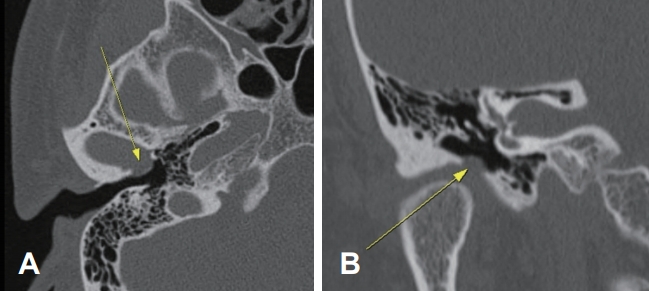

50세 남자 환자가 약 2주 전부터 자연히 발생한 우측 이충만감과 저작 시 우측 이명을 주소로 본원에 내원하였다. 약 20년 전에 악관절이 빠진 적이 있었으며, 이후 입을 벌리거나 다물 때 우측 악관절에서 소리가 나는 경향이 있었으나 특별한 치료는 받지 않았다. 그 외에 당뇨, 고혈압 및 특이적인 치과 수술의 병력은 없었다. 이내시경을 이용한 이학적 검사에서 우측 외이도 전하벽으로 돌출된 종괴가 관찰되었으며, 입을 다물 때는 돌출되었으나 입을 벌릴 때는 사라지는 양상이었다. 이 외에 고막을 비롯하여 다른 구조물에서는 특이적인 소견이 보이지 않았고, 이관 기능도 정상이었다. 시행한 측두골 전산화단층촬영에서 우측 외이도 전벽에서 약 3.5×5.8 mm의 골 결손으로 인해 우측 외이도 전하벽으로 연조직의 팽윤 소견을 보이고 있었다(Fig. 1). 순음청력검사상에서는 우측 기도청력 6 dB, 좌측 기도청력 9 dB로 정상 소견을 보였으며, 고막운동성 검사에서도 양측 A형으로 정상 소견을 보이고 있었다. 악관절 자체에 문제가 없는지 치과 자문을 의뢰하였으며 특이 소견이 없음을 확인하였다. 환자에게 우측 외이도의 선천적인 골 결손에 의해서 우측 악관절이 이탈하였으며, 증상이 없거나 일상생활에서 불편감이 크지 않을 경우 우측으로 무리하게 씹는 것을 조심하면서 수술적 치료 없이 보존적으로 지켜보는 경우도 있음을 설명하였으나 본 증례의 환자는 저작 시에 우측 이충만감으로 일상생활의 불편감을 느낀다고 호소하여서 수술적 치료를 시행하기로 하였다.